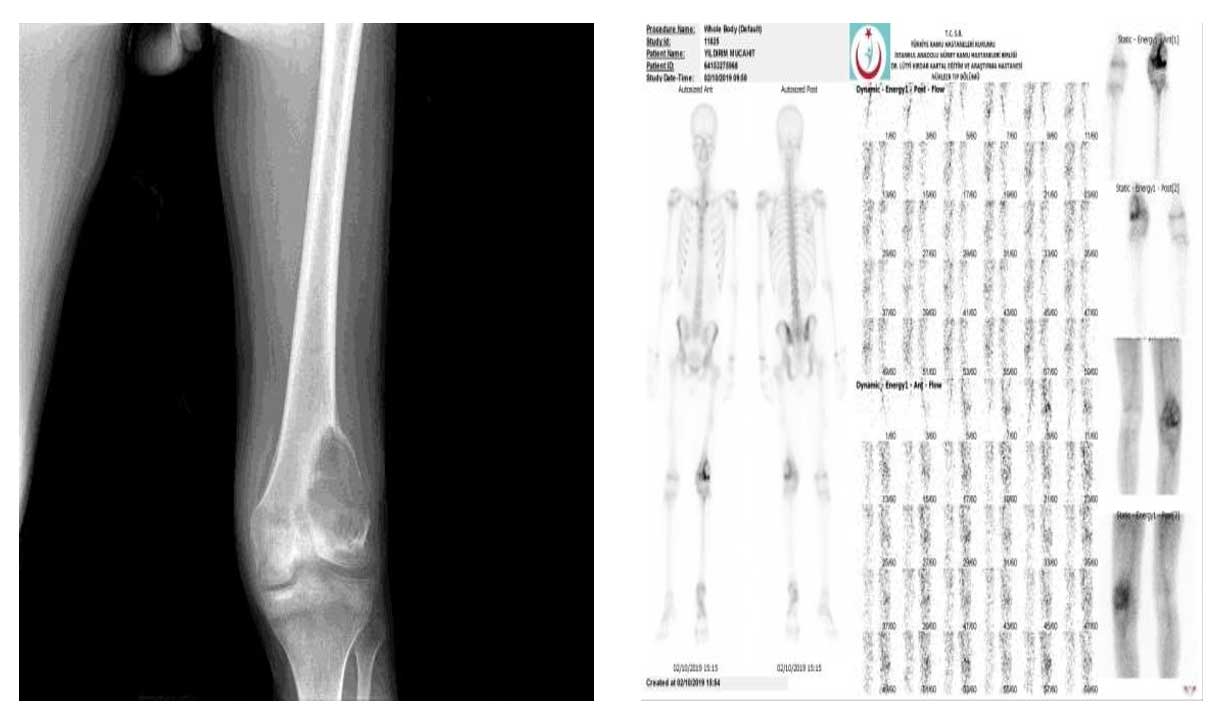

Vaka 30: Diz (Distal femur) Yerleşimli Osteosarkom

Distal femurda osteosarkoma bağlı gelişen patolojik kırık sonrası kemoterapi ve cerrahi tedavi uygulanan genç erkek hastamızda, tümörün tamamen çıkarılması ve diz fonksiyonlarının korunması hedeflenmiştir.

Distal femur yerleşimli osteosarkoma bağlı patolojik kırık nedeniyle başvurdu.

Ameliyat Öncesi: Röntgende distal femur lateralde litik lezyon, sintigrafide aynı lokalizasyonda artmış aktivite görülmekte.